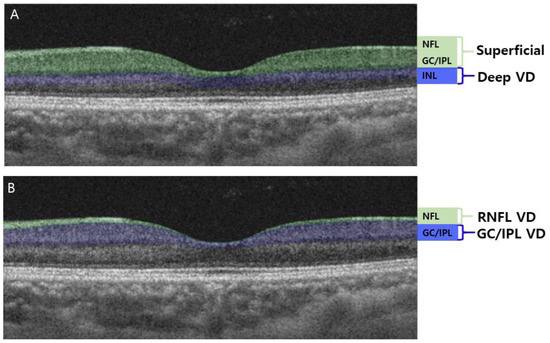

Внутрішній плексиформний шар (IPL – inner plexiform layer) - це один із шарів сітківки ока, розташований між внутрішнім ядерним шаром та шаром гангліозних клітин.